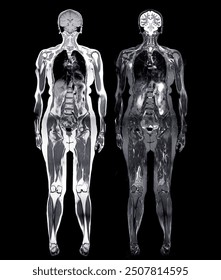

Whole-body MRI screening is fundamentally different from the MRI scans most people experience. When your doctor orders an MRI, it's usually because something's wrong. Maybe you have back pain, or your knee is swollen, or neurological symptoms that need investigation. In those cases, the radiologist knows what to look for. They can focus their expertise and attention on the specific body region and the specific problem.

Elective whole-body MRI works completely differently. The patient isn't sick. There are no symptoms. No red flags. The purpose is purely preventive—to find hidden problems before they cause symptoms. The scan typically covers the head, neck, chest, abdomen, and pelvis, generating hundreds of images that a radiologist must review in detail.

Whole-body screening scans are the opposite. They generate hundreds, sometimes over a thousand images. The radiologist reviewing these scans must mentally scan through all that data looking for anything abnormal. The challenge isn't just volume—it's that they're searching for anything wrong without knowing what might be wrong. They're casting an extremely wide diagnostic net.